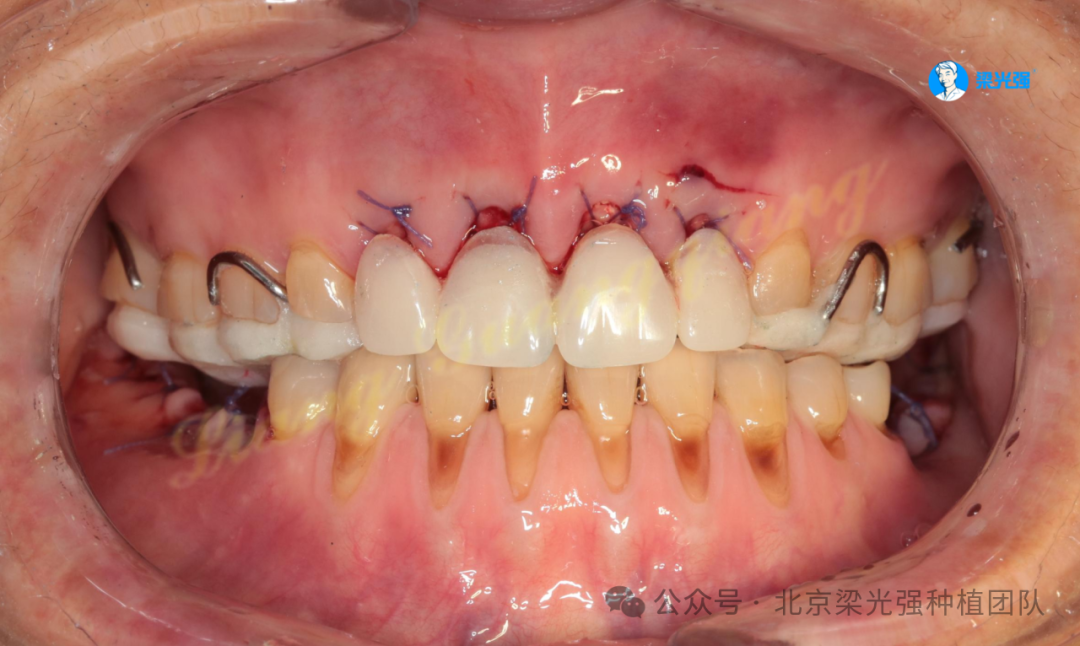

术后4个半月口内照,余留牙根据新的咬合高度全冠修复。

牙槽嵴顶用金刚砂车针去除上皮层。

安装愈合基台将去上皮的角化龈折叠翻转推到唇侧,以增加唇侧附着龈厚度。